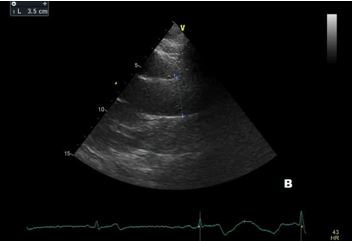

Aortic root diameter measurement should be performed in adults (>15 years) from the parasternal long-axis view during diastole using the L-L convention, preferring 2D measurements (Figure 1)(6).

In children and individuals under 15 years, aortic root diameter measurement is best measured in parasternal long-axis views during early to mid-systole, using the inner edge-to-inner edge technique (Figure 2)(7).